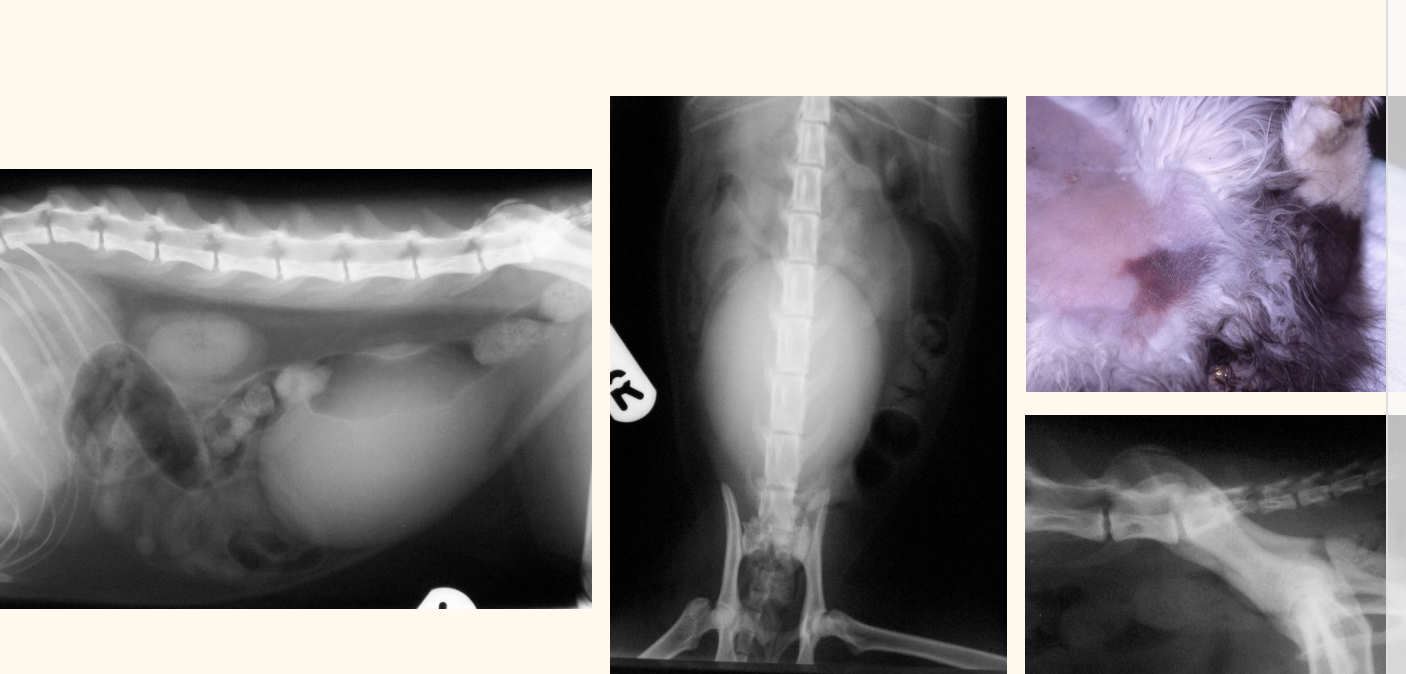

what deos this contrast radiography shoe

leakage of contrast into abdomen

urethrea lost…